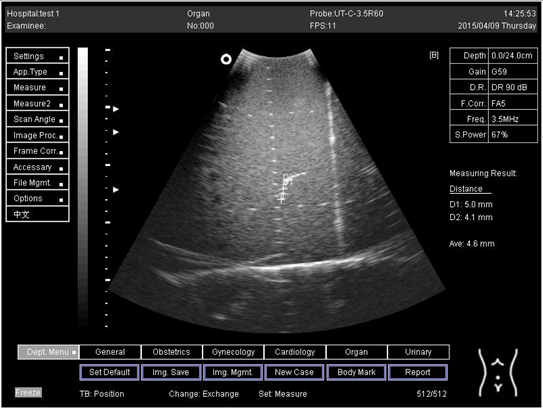

18.0Lateral resolution

Biomimetics 07 00130 i020

D1 = 5.0

D2 = 4.1